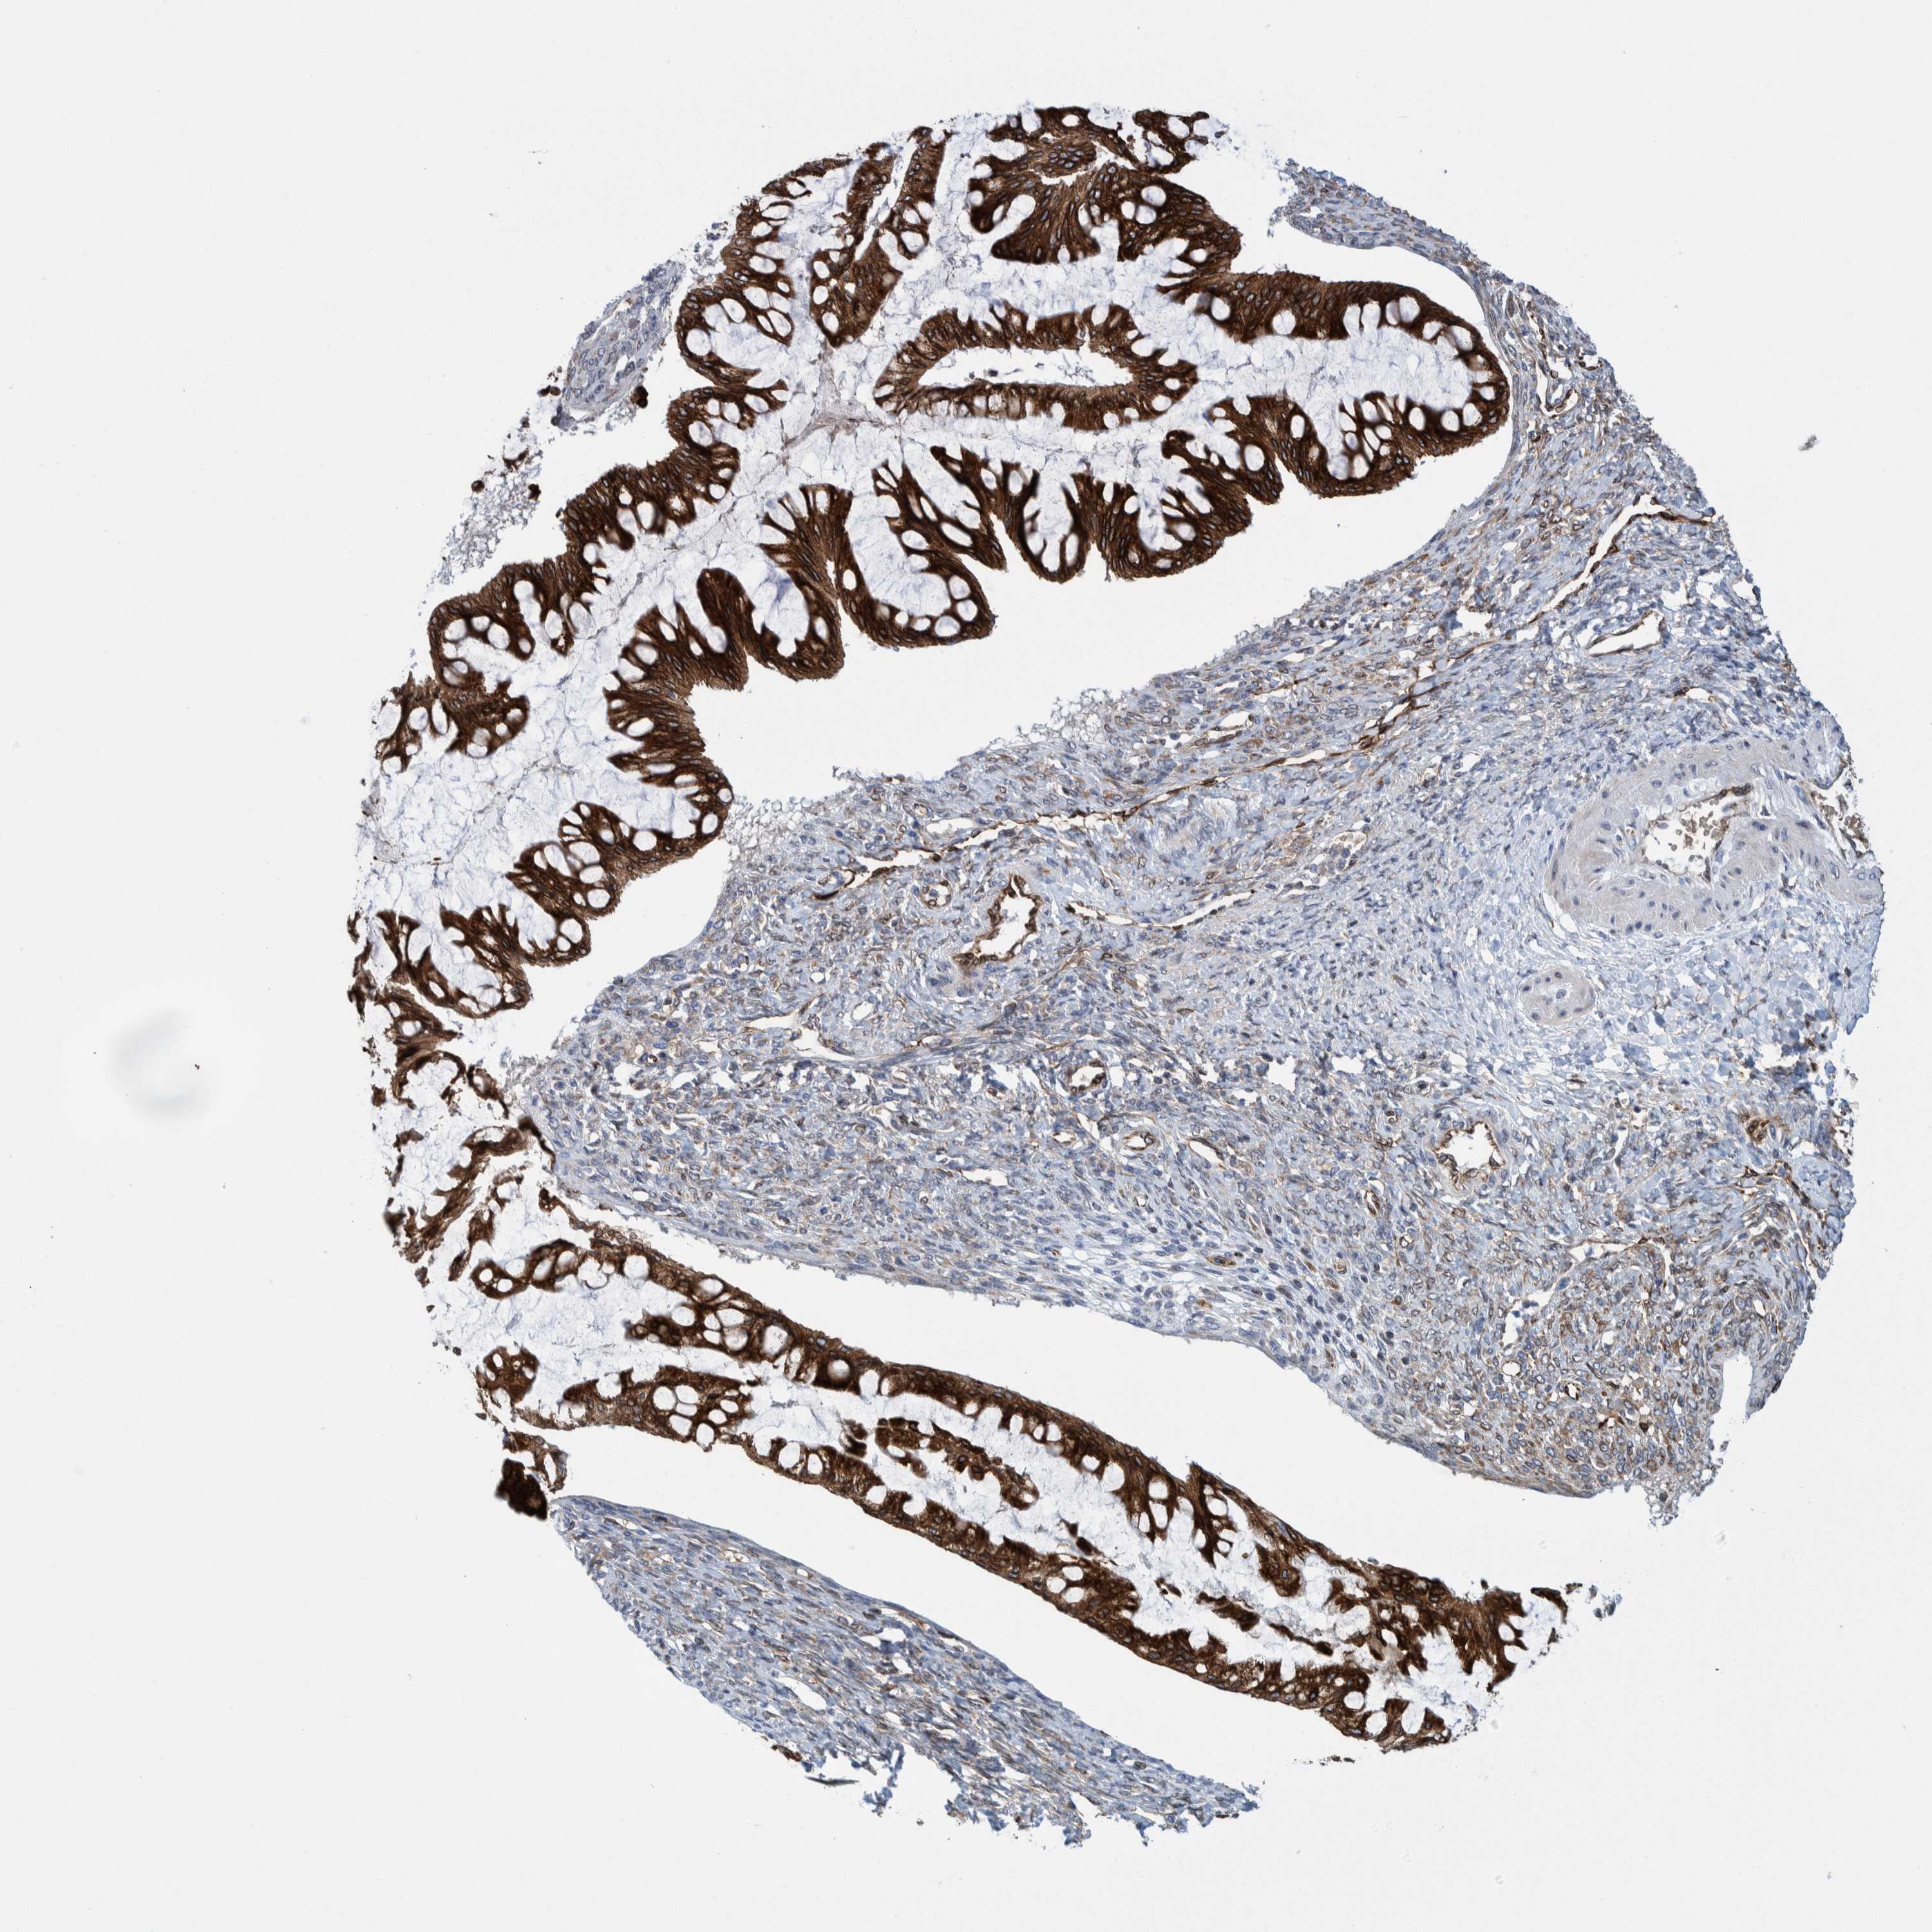

OVARIAN CANCER - Protein expressioni

A mouse-over function shows sample information and annotation data. Click on an image to view it in a full screen mode. Samples can be filtered based on level of antibody staining by selecting one or several of the following categories: high, medium, low and not detected. The assay and annotation is described here.

Note that samples used for immunohistochemistry by the Human Protein Atlas do not correspond to samples in the TCGA dataset.

Antibody stainingi

Antibody staining in the annotated cell types in the current human tissue is reported as not detected, low, medium, or high, based on conventional immunohistochemistry profiling in selected tissues. This score is based on the combination of the staining intensity and fraction of stained cells.

Each image is clickable and will lead to virtual microscopy that enables deeper exploration of all samples and also displays staining intensity scores, fraction scores and subcellular localization as well as patient and tissue information for each sample.

Antibody HPA023255

Staining

High

Medium

Low

Not detected

Intensity

Strong

Moderate

Weak

Negative

Quantity

>75%

75%-25%

<25%

None

Location

Nuclear

Cytoplasmic/membranous

Cytoplasmic/membranous,nuclear

Cystadenocarcinoma, serous, NOS

Carcinoma, endometroid

Cystadenocarcinoma, mucinous, NOS

Carcinoma, NOS